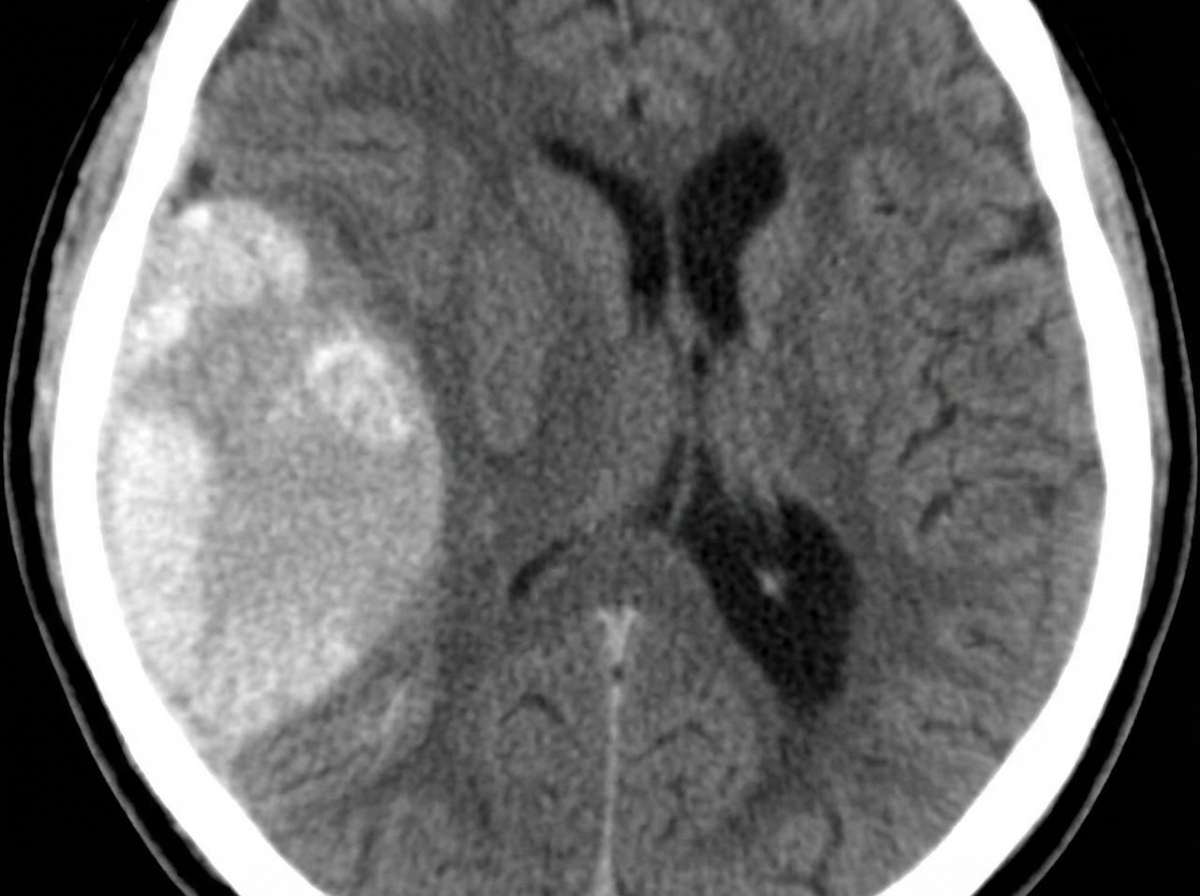

A 23-year-old man presents with a blunt force injury to the head from a baseball bat. He is currently unconscious, although his friends say he was awake and speaking with them en route to the hospital. He has no significant past medical history and takes no current medications. The vital signs include: temperature 37.0°C (98.6°F), blood pressure 165/85 mm Hg, pulse 50/min, and respiratory rate 19/min. On physical examination, there is a blunt force injury to the left temporoparietal region approximately 10.1–12.7 cm (4–5 in) in diameter. There is anisocoria of the left pupil, which is unresponsive to light. The patient is intubated and fluid resuscitation is initiated. A noncontrast computed tomography (CT) scan of the head is acquired and shown in the exhibit (see image). Which of the following is the most appropriate medical treatment for this patient?